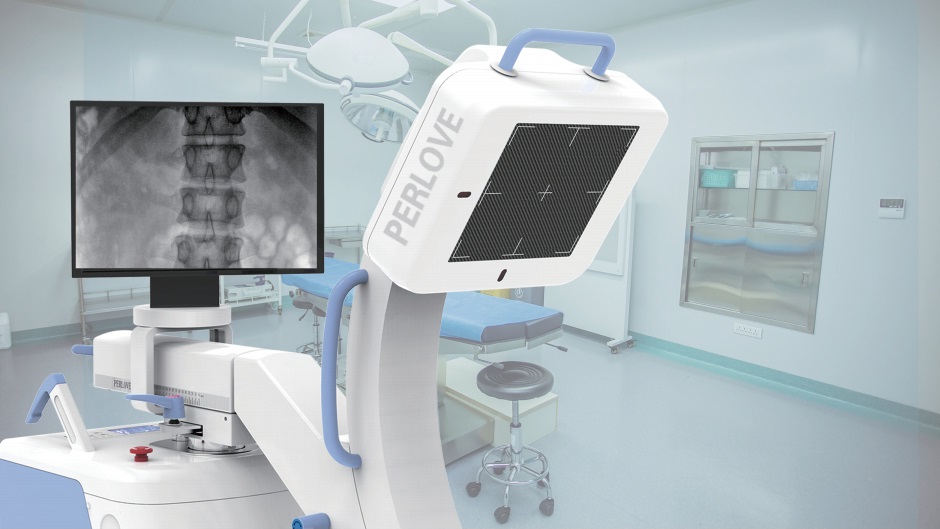

大尺寸动态平板探测器,高DQE、低噪声、图像清晰。采用多分辨率图像增强处理技术,不同部位不同图像处理算法,满足客户多样化的需求。

图形化操控界面设计:设有多种人体特征摄影参数,操作简便。双向红光十字定位系统:实现无射线下的高效定位。信息共享:遵循DICOM3.0格式接口,可无缝对接云PACS系统。

多角度自由旋转,满足患者复杂摆位需求。